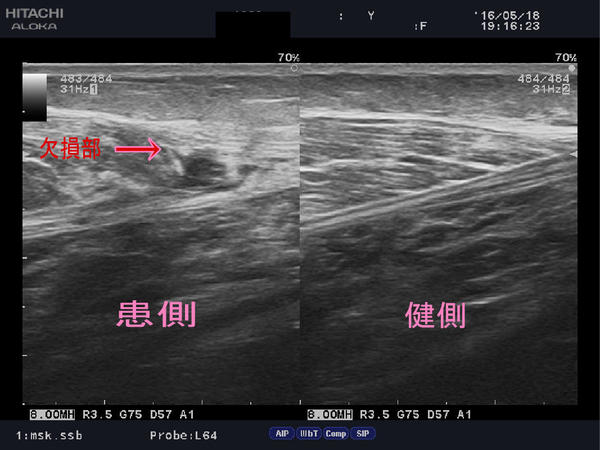

超音波診断装置で負傷部位を確認してみると、

ほんの数センチの欠損範囲なのにとても痛く、

損傷時の衝撃は大きく、筋肉の繊細さ、張力の強さを感じます。

hukurahagi.jpg